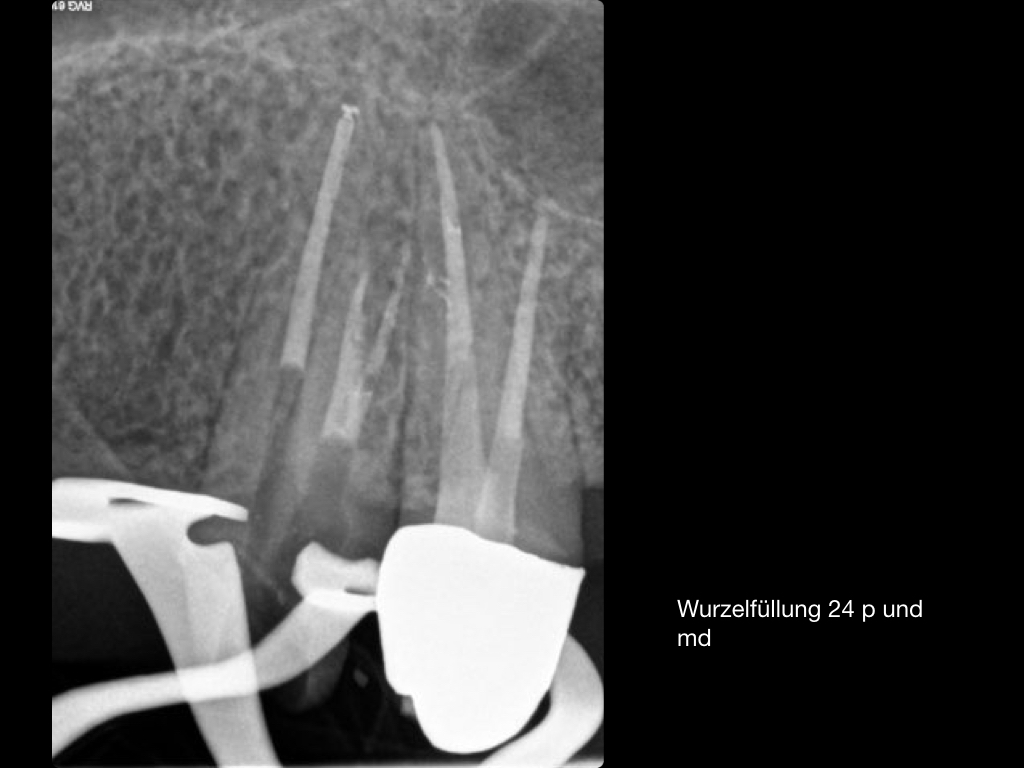

Es ist zu sehen … (2)